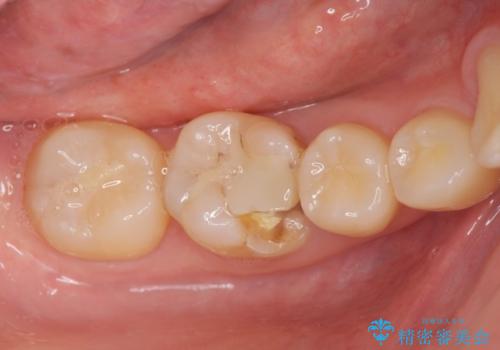

- 銀の詰め物が取れたとのことで来院。

詰め物の下には虫歯がありました。

白い物で治療して欲しいとのことで、セラミックの詰め物だと詰め物の範囲が大きく、割れてしまう可能性があるので

ジルコニアクラウン(被せもの)で治療を行いました。